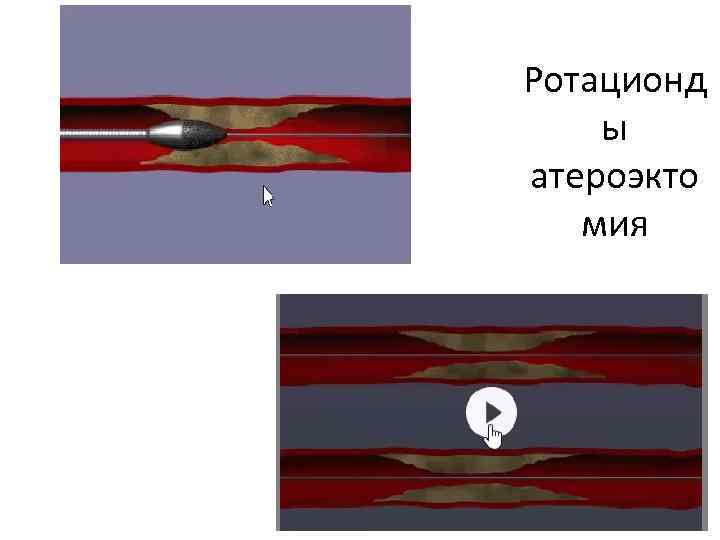

Тікелей атероэктомия Ротационды атероэктомия • Әктенбеген бляшка кезінде қолд • Аорт төм бөл. ж/е бифуркацияда • Әктенген, ұз 20 мм бляшка кез-де • Алмазды наконечнигі бар бур ар-ы бляшканы құмға айн-ы

Тікелей атероэктомия Ротационды атероэктомия • Әктенбеген бляшка кезінде қолд • Аорт төм бөл. ж/е бифуркацияда • Әктенген, ұз 20 мм бляшка кез-де • Алмазды наконечнигі бар бур ар-ы бляшканы құмға айн-ы

Ротационд ы атероэкто мия

Ротационд ы атероэкто мия